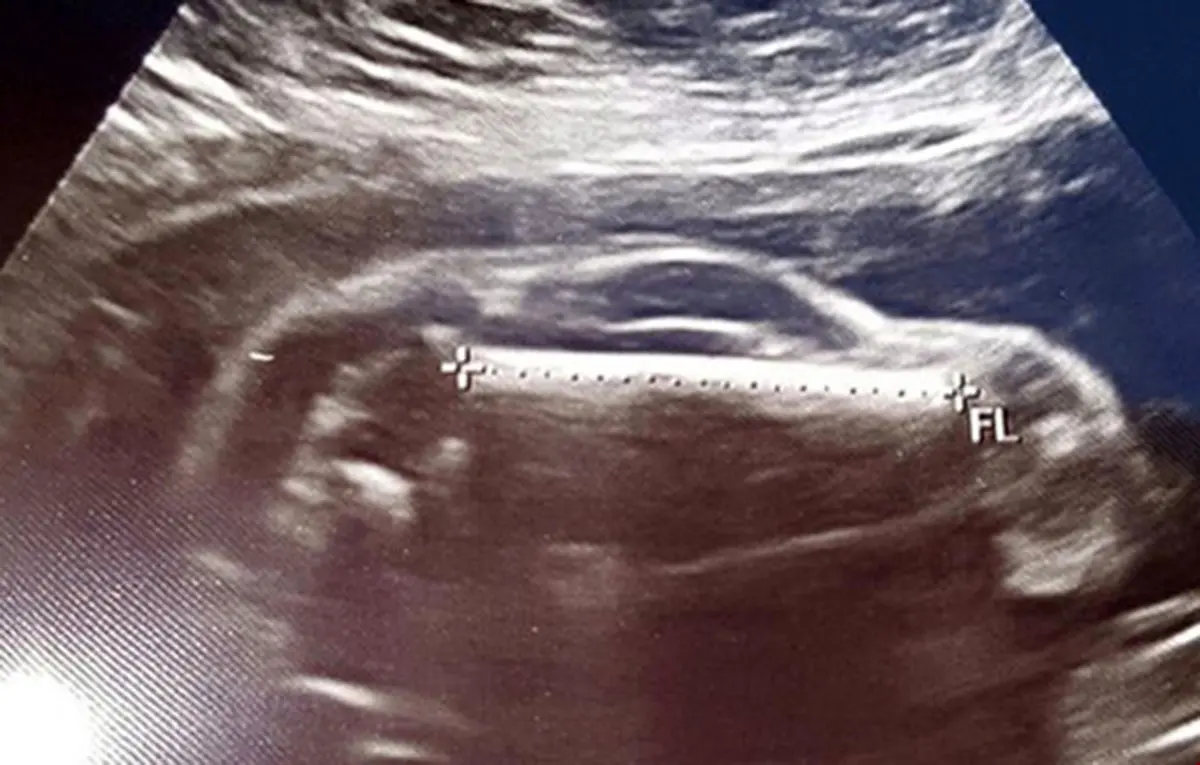

ماشین اسپرت در شکم یک زن حامله ! + عکس سونوگرافی

رکنا:ماجرای دیده شدن یک ماشین اسپرت در شکم زن حامله خیلی عجیب است.

یک زوج که برای سونوگرافی مراجعه کرده بودند تصویر عجیبی در سونوگرافی خود دیدند.مردی عکس سونوگرافی همسر خود را در اینترنت به اشتراک گذاشت و نوشت: همسر من یک خودروی اسپرت حامله است. این به اشتراک گذاشتن عکس درست بعد از دیدن این تصویر عجیب در شکم مادر اتفاق افتاد.کاربران اینترنت هم با او موافقت کردند که بچه آینده آنها قرار است شبیه یک خودروی اسپرت باشد.

پدر بچه در پست خود افزود که بچه آینده آنها قرار است که یک ماشین اسپرت پسر باشد.